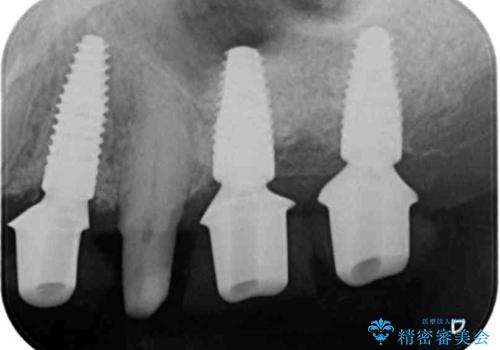

インプラント・ブリッジ補綴を含む、歯周病全顎治療

全体的な歯周病検査を行い、多数の残すことのできない抜歯の必要な歯を認めたため、残せる歯に対しての徹底的な歯周病治療、失った歯に対しブリッジ・インプラント治療を全顎的に行っていくこととしました。

長期間にわたる治療後、歯に対する意識も大きく変わりプラークコントロールも非常に良くなりました。

数ヶ月に一度のチェックをしっかりと行い、ブリッジ・インプラントが長期間使用できるようメンテンスを行っていきます。